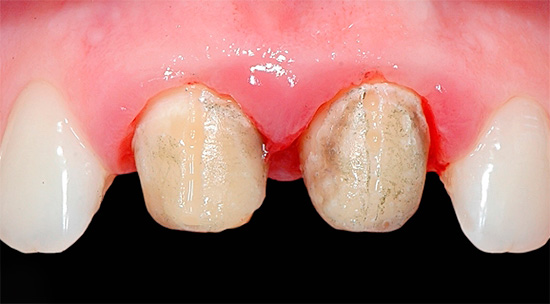

A foto abaixo mostra um exemplo de inflamação das gengivas em contato com as coroas: